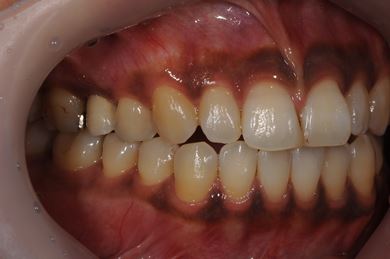

インプラントの症例写真 IMPLANT

| 治療内容 | インプラント2本(ソケットリフト、抜歯即日スピードインプラント)、メタルボンドセラミッククラウン3本(メタルボンドセラミック用土台1本)、ハイブリッドセラミックインレー4本 | ||||||||||||||||||||||||||||||||

| 治療期間 | 10ヶ月 |

治療前